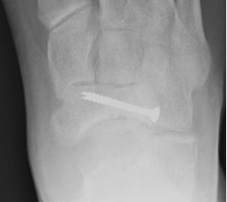

Locking plate

Paragon navicular plate Synthes navicular plate

AO foundation navicular locking plate technique

Displaced stress fracture treated with dorsal plate